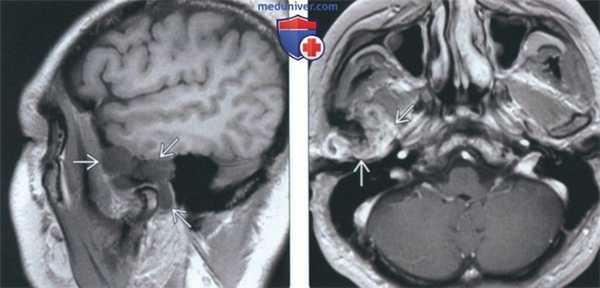

4. МРТ при первичном синовиальном хондроматозе ВНЧС:

• Т1 ВИ:

о МРТ позволяет дифференцировать тканевые пластинки между объемным образованием и окружающими мягкими тканями:

- Дает возможность отличить хондроматоз ВНЧС от опухоли околоушной железы

- В случаях интракраниального распространения позволяет исключить поражение височной доли

о Множественные гипоинтенсивные узлы в верхнем суставном пространстве

о Утолщение синовиальной оболочки

о Сепарация от суставного диска

• Т2 ВИ:

о Выпоте верхнем суставном пространстве ± вздутие:

- Слегка неоднородный гиперинтенсивный сигнал в неоссиицированных/необызвествленных хрящевых узлах

о В редких случаях выпот не обнаруживается, может наблюдаться сигнал неоднородной интенсивности, свидетельствующий о мягкотканном образовании или хрящевых узлах о Кольцевидный сигнал: гиперинтенсивная жидкость вокруг скоплений гипоинтенсивных узлов

• Т1 ВИ С+:

о Контрастное усиление синовиальной оболочки

(Слева) На аксиальной КТ у этого же пациента вдоль внутреннего, наружного, переднего края мыщелка визуализируются множественные обызвествленные/оссифицированные свободные тела различного размера. Су аавная капсула в значительной степени растянута.

(Справа) На косом корональном срезе (Т1) у этого же пациента в пределах растянутой капсулы визуализируются обызвествленные/оссифицированные свободные тела.

4. МРТ при хондросаркоме височно-нижнечелюстного сустава (ВНЧС):

о Сигнал низкой-промежуточной интенсивности по сравнению с серым веществом:

- Гипоинтенсивные очаги в опухоли могут быть отражать кальцинаты

о Гиперинтенсивный сигнал

о Гипоинтенсивные очаги (кальцинаты) обнаруживаются реже, чем на КТ

о Неравномерно контрастирующееся образование:

- Часто обнаруживаются «завитки» из контрастирующихся линий в матриксе опухоли

(Слева) На сагиттальной МРТ (Т1 ВИ) у этого же пациента вокруг мыщелка визуализируется многокамерное объемное образование, вовлекающее суставную ямку и большое крыло клиновидной коои.

(Справа) На аксиальной MPT (Т1 ВИ С+ FS) у этого же пациента определяется обширное контрааное усиление солидного объемного образования, окружающего мыщелок, что позволяет исключить его воспалительный характер.

(Слева) На аксиальной МРТ (Т2ВИ FS) у пациента с ХС левого ВНЧС определяется мягкотканный компонент с неоднородным, но в целом высокоинтенсивным Т2 сигналом, типичным для хондроидных опухолей. Точечные гипоинтенсивные очаги отражают внутриопухолевые кальцинаты.

(Справа) На корональной МРТ (Т1ВИС+ FS) у этого же пациента определяется интенсивное накопление контраста в объемном образовании сустава, что подтверждает его солидную структуру и позволяет исключить жидкость в суставе, растягивающую капсулу.